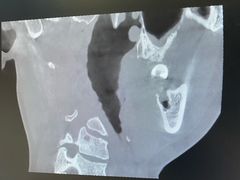

• 牙博士口腔品牌连锁(杨浦店)

• -牙博士口腔品牌连锁(杨浦店)

匿名用户 | 24-07-07